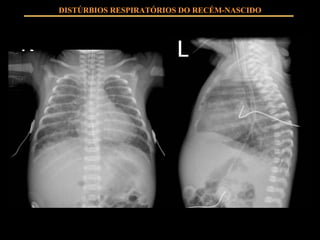

DISTÚRBIOS RESPIRATÓRIOS DO RECÉM-NASCIDO VM – Indicações clínicas: Hérnia diafragmática Esforço respiratório grave Apnéia recorrente ( >  2/h) Distúrbio hemodinâmico grave Asfixia grave Apnéia por distúrbio neuro-muscular congênito Uso de drogas depressoras de SNC

DISTÚRBIOS RESPIRATÓRIOS DO RECÉM-NASCIDO VM – gasométricas: pO2 < 50 mmHg SO2 < 86% pCO2 > 60 mmHg FiO2 > 60-80% CPAP 5-6 cm H2O Acidose metabólica pH < 7,20 (< 6h) pH < 7,25 (> 6h)